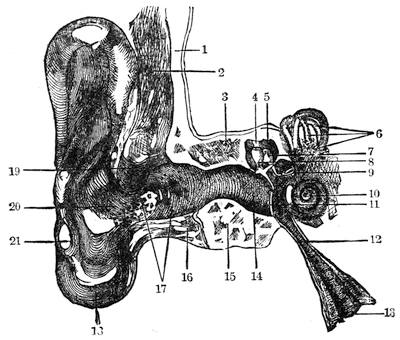

| CHAPTER XV.—ACOUSTICS. | |

| The Ear and Hearing—Physiology of Hearing and Sound—Sound as Compared with Light—What is Sound?—Velocity of Sound—Conductibility—The Harmonograph | 166 |